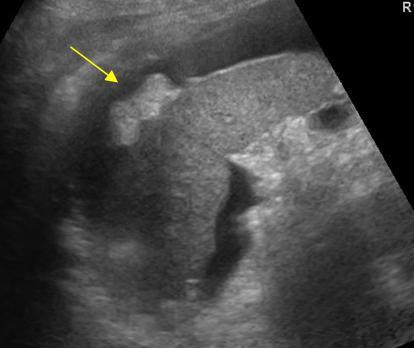

Что же показывает УЗИ брюшной полости? Прежде всего, диагност проводит оценку:

- размеров, положения, структуры и формы печени;

- наличия включений, таких как камни;

- общего состояния желчного пузыря, его протоков и сосудов полости;

- поджелудочной железы, селезенки и почек.

По результатам эхограммы, полученным с помощью ультразвукового аппарата, доктор делает заключение общего состояния верхней части брюшной полости. Обследуемый получает бланк-протокол с зафиксированными нормативными показателями и конкретными данными.

Какие органы показывает изображение УЗИ брюшной полости? Процедура позволяет медику получить информацию о:

- печени;

- селезёнке;

- почках;

- поджелудочной железе;

- жёлчном пузыре;

- жёлчных протоках;

- кровеносных и лимфатических сосудах.